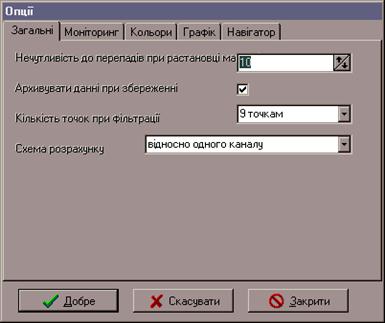

Діалогове вікно "Опції":

Всі опції розбиті на 5 класів (рисунок 8.7):

"Загальні" - опції, використовувані при обчисленнях і при збереженні даних:

Рисунок 8.7 – Діалогове вікно "Опції" (загальні)

"Нечутливість до перепадів" – параметр, що впливає на якість розміщення маркерів, "Архівувати дані при збереженні" - якщо параметр включений, те дані записуються у файл даних у стиснутому LZH-компресією вигляді, що приводить до збереження вільного місця на носії інформації, "Кількість точок при фільтрації" - фільтрація полягає в параболічній апроксимації (нерекурсивний фільтр низьких частот), тому це число (5,7 чи 9 точок) указує скільки точок буде впливати на значення в даній точці. 9 точок дає максимальне згладжування, "Схема розрахунку" - визначає вигляд звіту - як при діагностиці остеохондроза (дані до і після сеансу) чи щодо однієї еталонної хвилі, "Моніторинг" - визначає параметри інтерфейсу з апаратною частиною комплексу (рисунок 8.8).